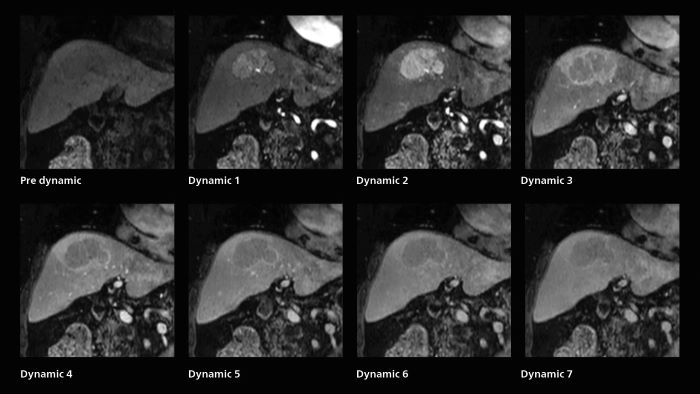

Also in dynamic MRI of the liver Dr. Katahira sees important improvements. While previously his scan used 9 seconds for a 5 mm slice, SmartSpeed now allows him to achieve a thin slice volume scan (1.6 x 2.1 x 2mm) with double arterial phase using acceleration factor 8. He indicates this is very useful for the radiologist when diagnosing, especially because it can provide a high temporal resolution.

Dynamic MRI of liver using SmartSpeed

A patient was referred for MR imaging of HCC. A double arterial volume dynamic study was performed. Since it is a volume dynamic study, it can also be evaluated using MPR images. Performed on Elition X.

Fast dynamic liver MRI: volume dynamic study of 1.05 min, 1.6 x 1.8 x 2.0 mm, 200 slices

The hospital’s routine ExamCard for dynamic MRI of the liver uses total scan duration 1:05 min, dynamic scan time 9.2 sec, 1.6 x 1.8 x 2.0 mm, 200 slices, acceleration factor 8.